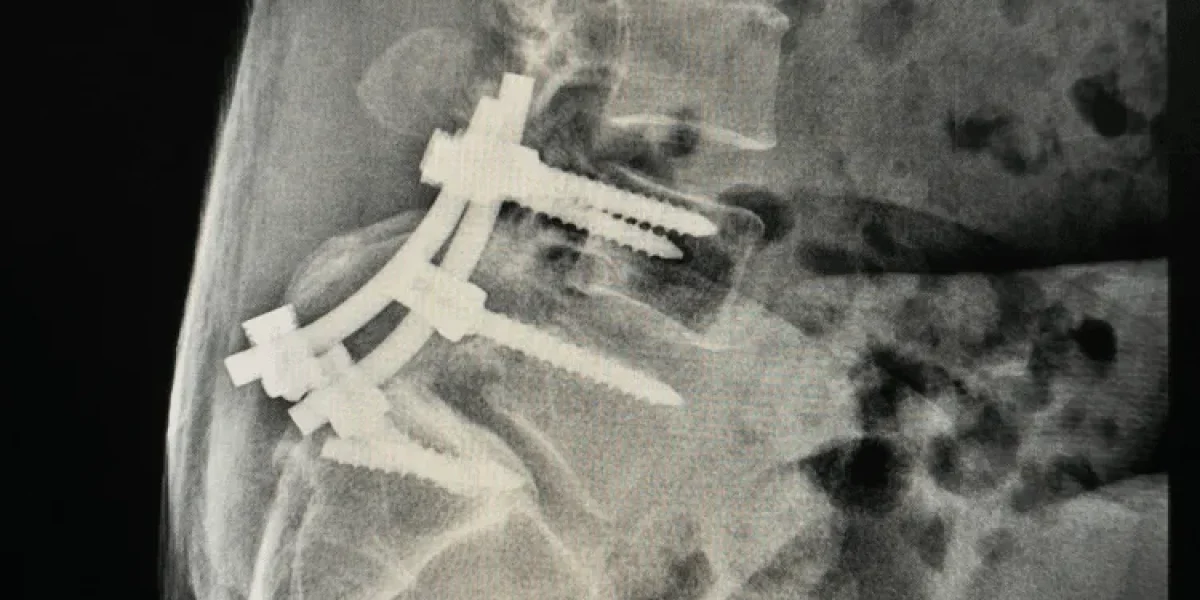

The surgery requires bone grafting to form a bridge between the affected vertebrae, with placement of screws, plates and rods into healthy bone to hold it all together. The result, depending on the number of levels (number of vertebrae affected) is a spine that no longer moves naturally, with healthy bone that is overly stressed and may become compromised.